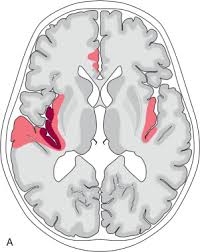

Two subtypes are recognized which differ in demographics, virus, and pattern of involvement. Become a gold supporter and see no ads. Bilateral temporal lobe t2 hyperintensity refers to hyperintense signal involving the temporal lobes on t2 weighted and flair imaging. Hypertrophic pachymeningitis is a condition where there is localized inflammatory thickening of the dura. Limbic encephalitis, mca ischaemia, tumours, effects of seizures) hyperintense t2 signal in the medial temporal lobes, inferior frontal lobes and insula basal ganglia are usually spared Reference osborn a, et al. Given the history of fever and seizures coupled with the mri findings of bilateral mesial temporal lobe changes, herpes encephalitis requires clinical consideration. The changes spare the basal ganglia, a feature which is helpful in distinguishing an mca infarct with hemorrhagic transformation from herpes simplex encephalitis, the diagnosis in this case. Mri demonstrates extensive edema in the right temporal lobe with areas of intrinsic high t1 signal, in keeping with hemorrhage. It is estimated to occur in ~2% of pati. The differential diagnoses include limbic encephalitis (paraneoplastic), gliomatosis cerebri, and status epilepticus. It is reasonable to obtain an mri when patients are asymptomatic to ensure that no other abnormality is present which may be causing a recurrent chemical meningitis (e.g. Axial t2 prominent swelling, increase t2 signal involving the left temporal lobe and insular cortex.

Clinico Radiological Spectrum Of Bilateral Temporal Lobe Hyperintensity A Retrospective Review Abstract Europe Pmc

Clinico Radiological Spectrum Of Bilateral Temporal Lobe Hyperintensity A Retrospective Review Abstract Europe Pmc from europepmc.org

Herpes simplex (hsv) encephalitis is the most common cause of fatal sporadic fulminant necrotising viral encephalitis and has characteristic imaging findings. The differential diagnoses include limbic encephalitis (paraneoplastic), gliomatosis cerebri, and status epilepticus. The basal ganglia are usually spared. Note the high signal in the caudate heads and putamen on flair. Bilateral temporal lobe t2 hyperintensity refers to hyperintense signal involving the temporal lobes on t2 weighted and flair imaging. It is reasonable to obtain an mri when patients are asymptomatic to ensure that no other abnormality is present which may be causing a recurrent chemical meningitis (e.g. For a general discussion, and for links to other system specific manifestations, please refer to the article on hydatid disease. Radiopaedia is free thanks to our supporters and advertisers.

Axial t2 prominent swelling, increase t2 signal involving the left temporal lobe and insular cortex. It is estimated to occur in ~2% of pati. Become a gold supporter and see no ads. This patient went on to have hsv encephalitis proven on csf pcr. A brain biopsy was performed and the histology was consistent with encephalitis. The differential diagnoses include limbic encephalitis (paraneoplastic), gliomatosis cerebri, and status epilepticus. Multilocularis.the larval stage is the cause of hydatid disease in humans 1. It is usually bilateral but asymmetrical. Spinal hydatid disease is an uncommon manifestation of hydatid disease, caused by the larval stage of echinococcus granulosus, or less commonly e. Limbic encephalitis, mca ischaemia, tumours, effects of seizures) hyperintense t2 signal in the medial temporal lobes, inferior frontal lobes and insula basal ganglia are usually spared It is reasonable to obtain an mri when patients are asymptomatic to ensure that no other abnormality is present which may be causing a recurrent chemical meningitis (e.g. 10 public playlist includes this case Pcr was repeated on the biopsy specimen and was positive for hsv.